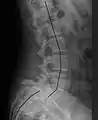

| X-ray of the lateral lumbar spine with a grade III anterolisthesis at the L5-S1 level | |